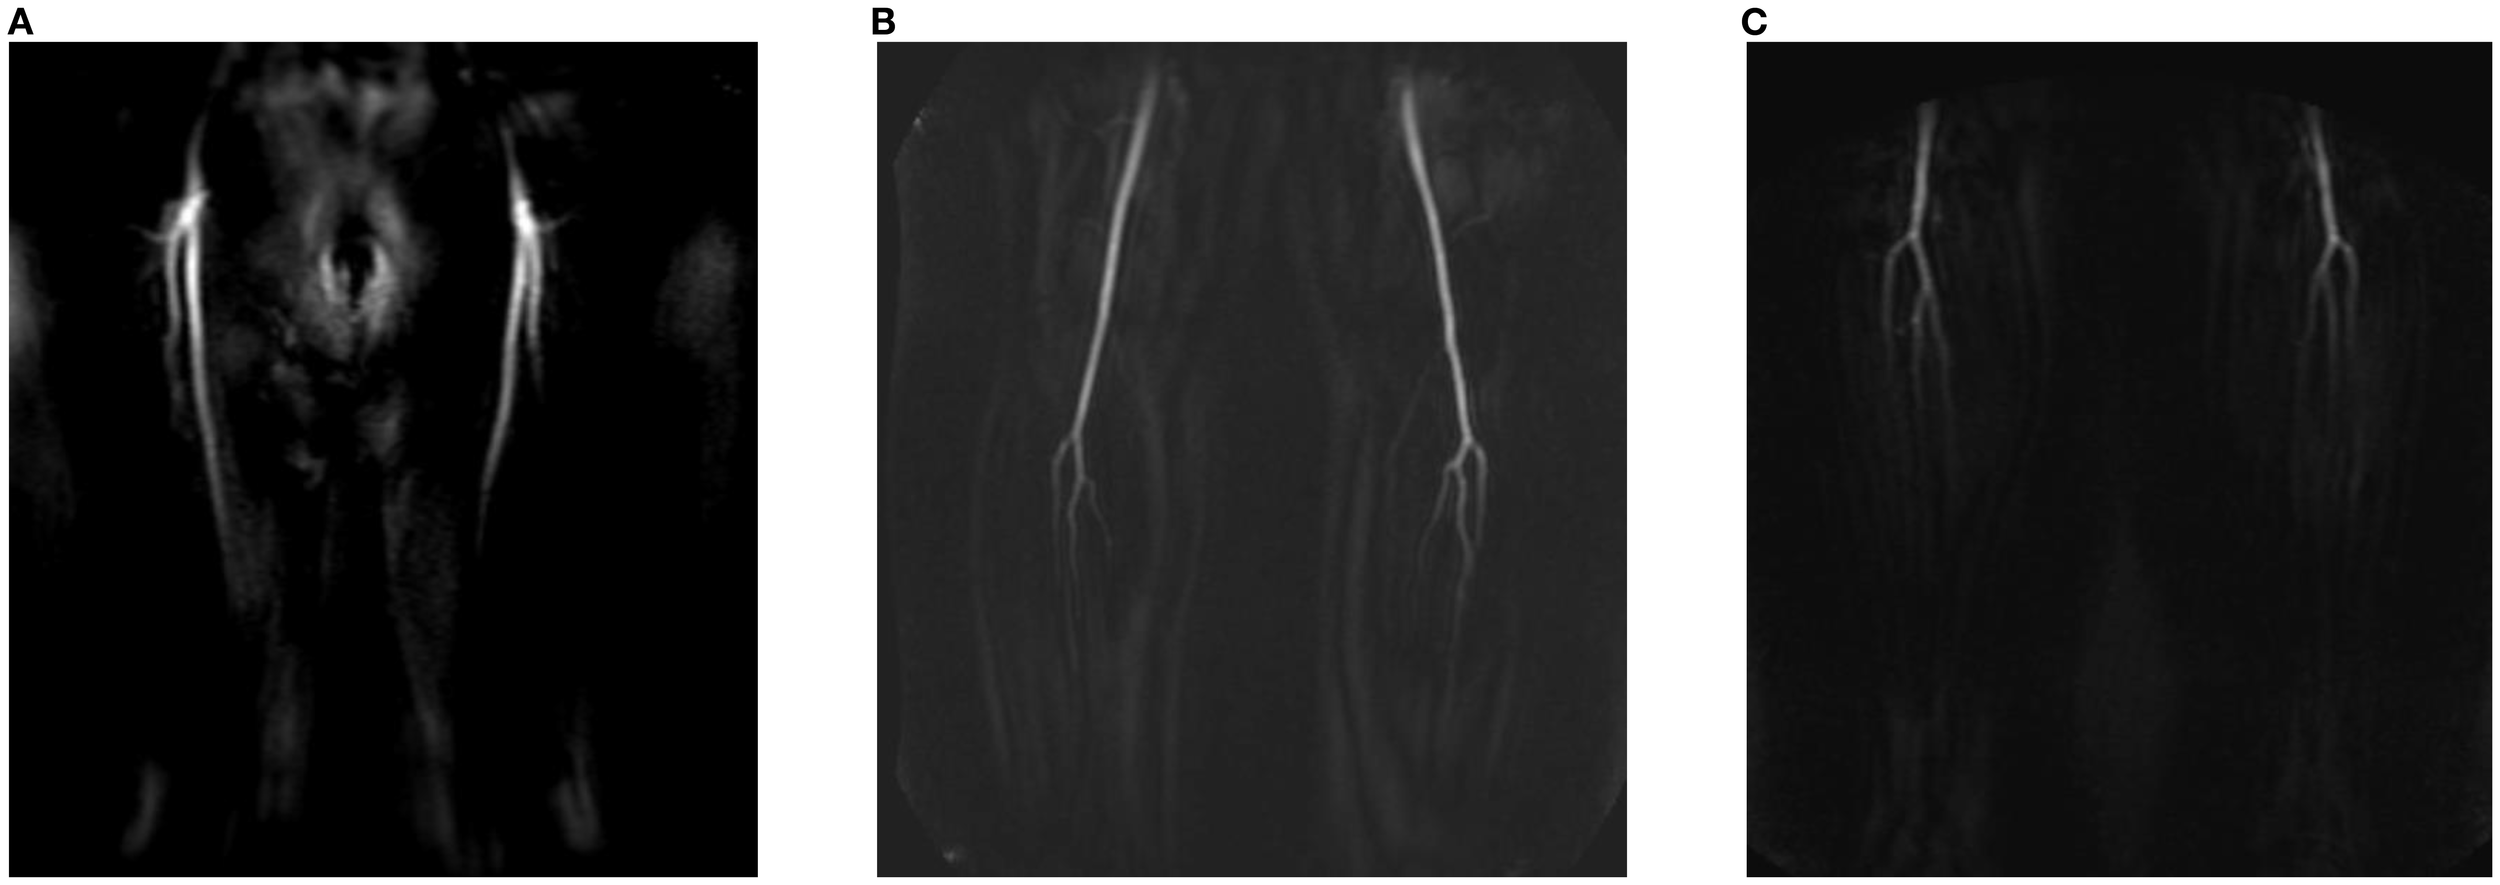

Centra k-space acquisition is used for contrast filling, starting two seconds after fluoroscopic triggering. For optimal perforator filling in the head and neck cancer patient population, the arterial mDIXON scan is triggered when vascular images are seen as shown in Figure 3. For ALT patients, branching of the lateral circumflex femoral artery (LCFA) is visible and contrast fills half of the upper leg. For MSAP and FFF patients, the popliteal trifurcation is visible and contrast fills the upper third of the lower leg. Figure 4 displays examples of arterial mDIXON Maximum Intensity Projection (MIP) images alongside corresponding axial slices, illustrating visible perforators in patients scheduled for surgery with ALT and FFF reconstruction.

Figure 3. View of BOLUSTRAK image when dynamic scan is started for (A) anterolateral thigh flap, (B) medial sural artery perforator flap, (C) fibula free flap.

Figure 4. Contrast-enhanced mDIXON arterial Maximum Intensity Projection (MIP) images with corresponding axial slices, in which perforators are indicated by arrows. The left panel shows the upper leg for the anterolateral thigh flap, while the right panel depicts the lower leg for the fibula free flap.